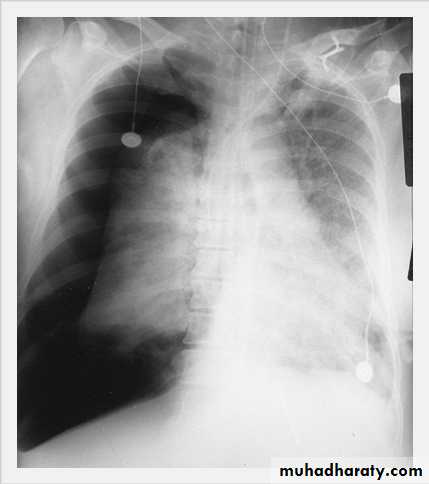

Tension Pneumothorax. Portable chest film in a 43-year-old woman with ARDS shows a large right pneumothorax with mediastinal shift and ipsilateral diaphragmatic depression, suggesting tension.

Air was evacuated under pressure during emergent placement of a right chest tube.

Massive pleural effusion with mediastinal shift to the left.

(A) Chest radiograph(B) CT coronal reconstruction. A massive effusion displaces the mediastinum to the left. CT shows the important pleural effusion together with the enhanced atelectatic left lung.

Note also the depression of the right hemidiaphragm (arrows).